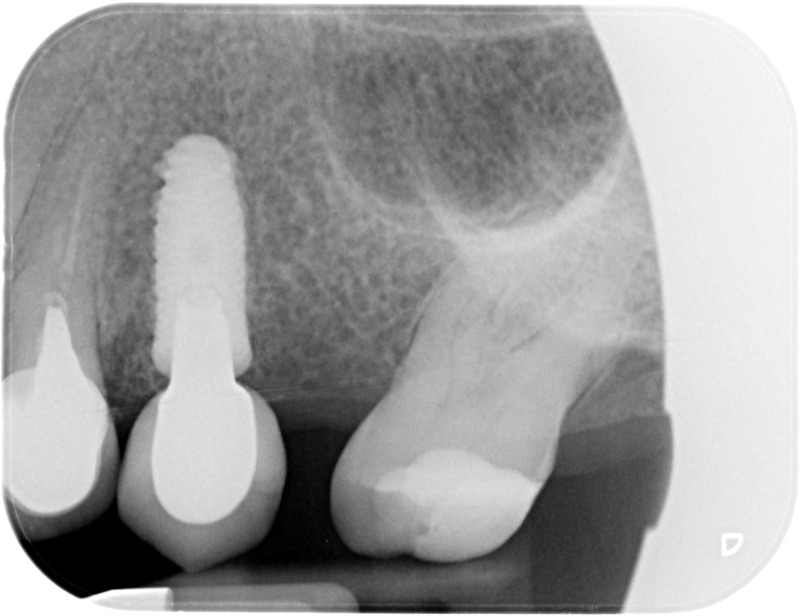

• Couronnes sur implants : Lorsqu’un implant est posé en remplacement des racines d’une dent, il est conçu pour recevoir d’abord un pilier vissé puis une couronne céramique. Le couple couronne - implant se substitue à la dent manquante pour en assurer les mêmes fonctions. Nous pouvons également adapter un bridge sur plusieurs implants dans le cas d’un édentement plus important.